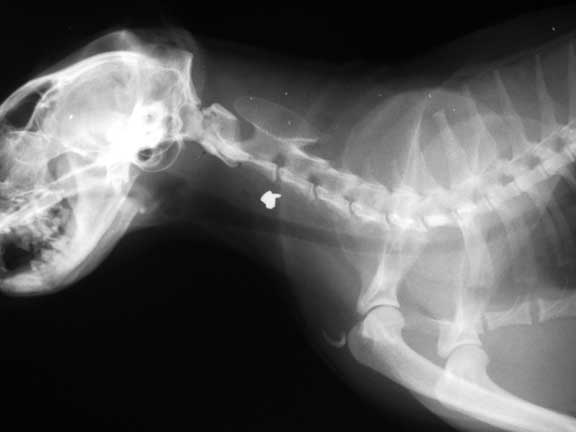

The horizontal tube is a feeding tube (called an esophatogomy tube) in the esophagus of this cat. It is used in cats that cannot eat due to a fractured jaw, or cats with a liver disease called hepatic lipidosis.

A pellet in the neck